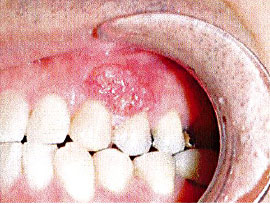

腫瘍1 腫瘍2

3. 口の中のできもの(良性腫瘍・悪性腫瘍)

良性腫瘍や悪性腫瘍(いわゆる、がん)は、歯ぐき、舌、頬粘膜、さらには顎の骨の中にも出来ることがあります。いずれも小さいうちに発見されると良いのですが、中でも良性腫瘍は痛くないまま大きくなるため、気づいた時にはかなりの大きさになっていることが多いです。また、悪性腫瘍では、口内炎がなかなか治らないなどで受診した時に発見されることも少なくありません。当院の定期検診では、歯だけでなく、お口の中全体を検診しています。